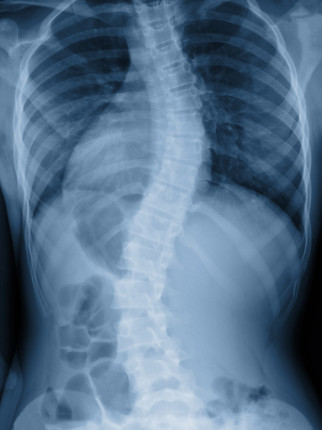

Scoliosis of spine

Genuine misaligned vertebrae: a scoliosis

Real “misaligned vertebrae”

A scoliosis is a sideways bend in the spine. A lot of conditions described as scoliosis are relatively minor bends such the “kink” caused in the dysfunction example above. However, there are rare conditions such as shown in this x-ray where a spine will develop a far more severe scoliosis.